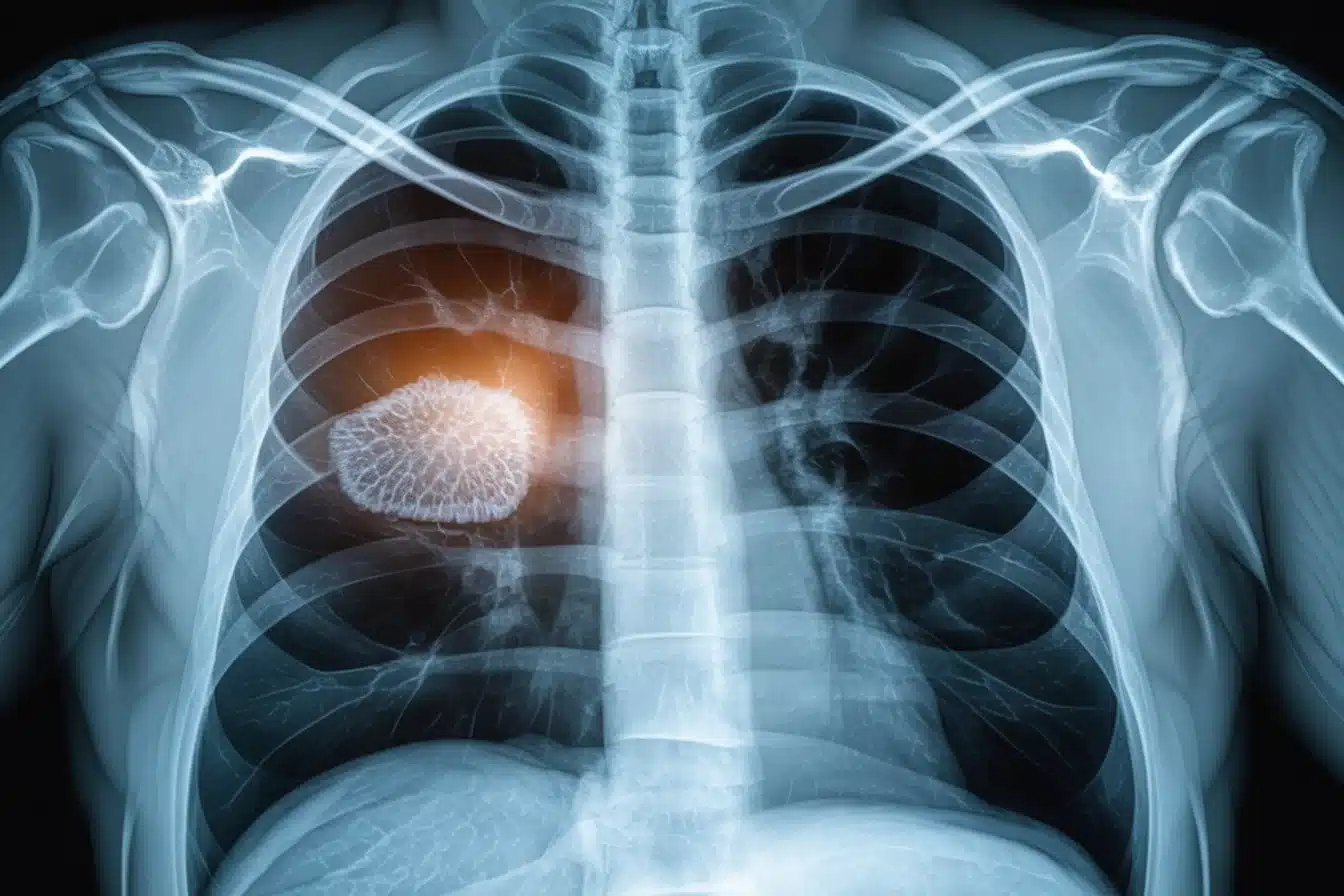

https://syndicat spel.fr//wp content/uploads/eau dans les poumons esperance de vie

Symptômes Et Diagnostic

L’œdème pulmonaire, caractérisé par une accumulation de liquide dans les alvéoles, entraîne des signes cliniques alarmants. Une identification rapide des symptômes et un diagnostic précis jouent un rôle crucial.

Méthodes De Diagnostic Utilisées

Pour confirmer la présence de liquide dans les poumons et identifier la cause sous-jacente, j’utilise plusieurs outils. L’auscultation peut révéler des crépitements typiques dans les poumons. Une radiographie thoracique permet de visualiser l’étendue de l’accumulation de liquide en 15 à 30 minutes. L’échocardiographie est essentielle pour évaluer la fonction cardiaque. Je sollicite également une mesure des gaz du sang (ABG) pour examiner les niveaux d’oxygène et de dioxyde de carbone, ainsi qu’un dosage du BNP (Brain Natriuretic Peptide), un marqueur indiquant un stress cardiaque. Enfin, si nécessaire, un scanner thoracique fournit des détails supplémentaires pour poser un diagnostic précis et orienter le traitement.